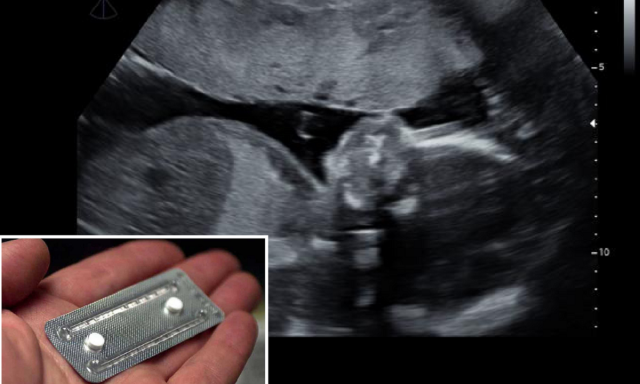

Este tipo de aborto es el denominado aborto farmacológico, consiste en tomar dos medicamentos en dos fechas distintas que, combinados, provocan la expulsión del contenido del útero. Primero se toma la Mifepristona, "fármaco que bloquea la producción de progesterona": bloquear su producción supone algo así como asfixiar al feto. Segundo se toma el Misoprostol, "que es el que provoca la expulsión de la gestación", este medicamento produce contracciones en el útero, es decir, se expulsa mediante un fuerte sangrado el bebé que previamente has asfixiado.